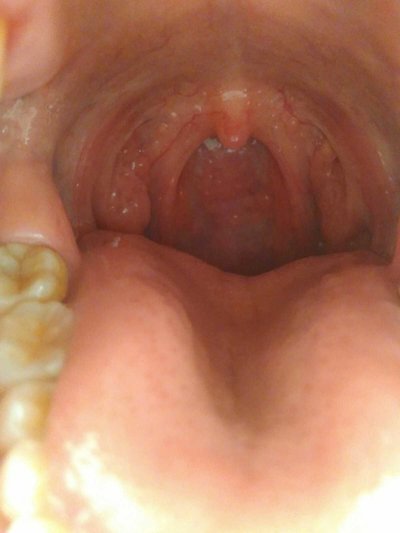

Examination showed congestion and swelling of pharyngeal mucosa, dark red, increased secretion. The mucosa of pharyngopalatal arch swelled. The lymphoid follicles in the posterior pharyngeal wall were swollen and congested. The soft palate and tonsils are also congested. Sometimes we can see uvula dropsy and soft palate swelling. In patients with severe infection, the pharyngeal lymph cord may be red and swollen. At the same time, patients can have acute inflammatory changes of nasal mucosa. When the neck pain may touch the swelling lymph node, has the tenderness.